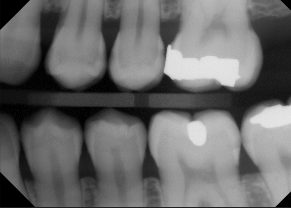

horizontal bone loss

parallel movement of alveolar crests towards the apex of the tooth

mild horizontal bone loss

blunting of alveolar crests and slight loss of height

loss of height around multiple teeth may involve furcation

moderate horizontal bone loss

moderate to severe horizontal bone loss